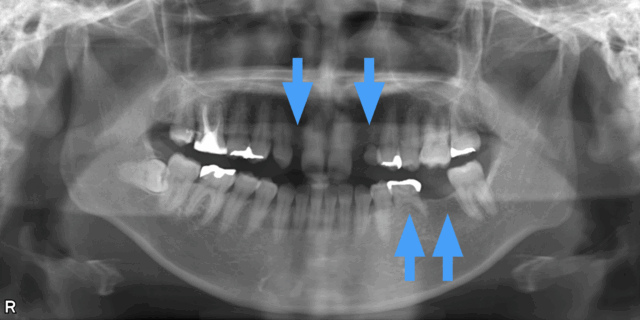

抜けそうな乳歯を抜歯してマウスピース矯正で実際に治療した症例

矯正治療前

抜けそうな乳歯があったので乳歯を抜歯してマウスピースで矯正して治療することにしました。

矯正治療計画

検査の結果、乳歯の根っこが吸収しており近々乳歯が抜けてしまう事が分かりました。

乳歯を抜いた後にできるスペースを利用して歯のガタガタも治す治療計画をたてました。